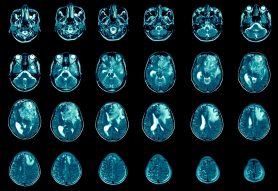

How is glioblastoma diagnosed?

Neurologic imaging with an MRI of the brain is often the first step. Brain imaging showing contrast-enhancing masses can be suggestive of glioblastoma.

Most cases can be definitively diagnosed after surgery through histological testing. This takes place when a neuropathologist examines tissue or cells under a microscope to help confirm a glioblastoma diagnosis.